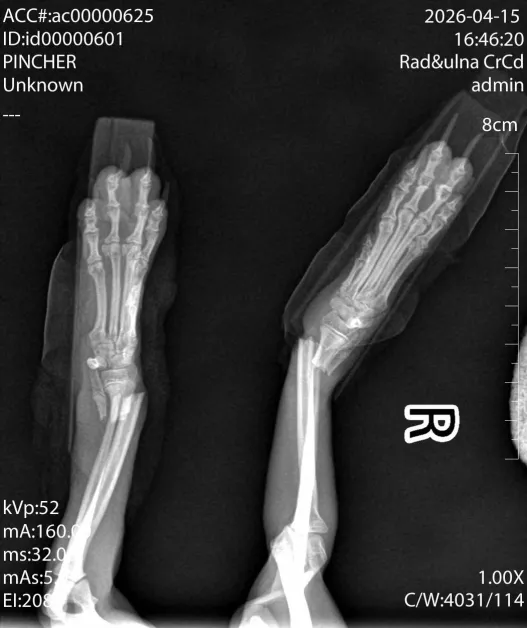

Всичко започва в етническия квартал, където група деца са си играли с младото куче. В разгара на забавлението, животното е било изпуснато от голяма височина. Резултатът е смразяващ – двата предни крака на Айра са счупени, оставяйки я напълно безпомощна.

Хлапетата все пак занесли пострадалото животно до ветеринарна клиника „Провет“, но в момента, в който лекарите съобщили тежката диагноза и необходимостта от скъпоструваща операция, децата се изплашили и избягали, оставяйки кученцето само в клиниката – безпомощно, в шок и без собственик.

Цената за операциите на двете крачета възлиза на 1500 евро. Сума, която е непосилна за една организация, но напълно постижима, ако се обединим като общество. В момента Айра се намира в сигурните ръце на специалистите от „Провет“, но съдбата ѝ зависи от даренията на добри хора.